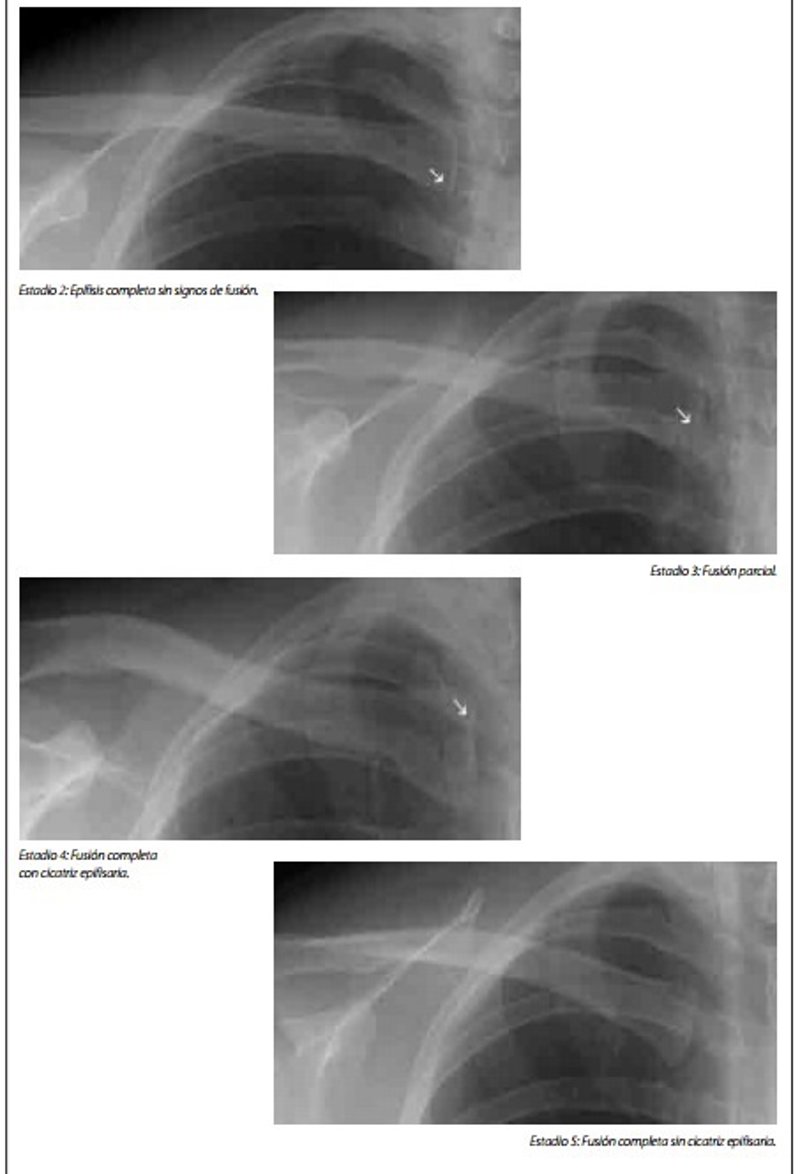

Pruebas oseométricas de determinación de la edad, no acompañados